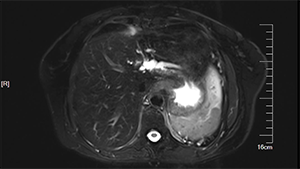

术中影像引导的肝S7、8段定构切除治疗结肠癌肝转移

作者:王勋 | 作者单位:解放军总医院第一医学中心

发布时间:2020-09-03 21:37:33